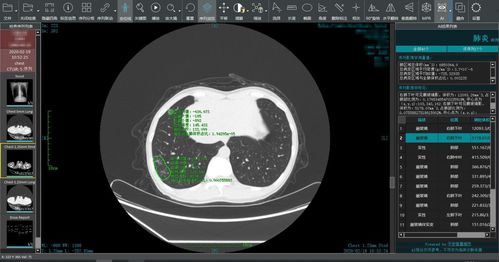

我们需要明确医院CT图像的重要性,CT(Computed Tomography)即计算机断层扫描,是一种常见的医学影像检查手段,通过CT扫描,医生可以获得患者体内器官、组织的高清三维图像,为疾病的诊断和治疗提供重要依据,CT图像在医疗领域具有极高的价值。

随着移动互联网的普及,许多人希望能够在手机上查看医院的CT图像,从技术角度来看,手机端查看CT图像存在诸多局限性,手机的屏幕尺寸和分辨率有限,无法满足高清、大尺寸的医学影像显示需求,手机端缺乏专业的医学影像处理软件和设备,无法对CT图像进行准确的解读和分析,手机端的安全性、隐私性和稳定性也无法满足医学影像的特殊需求。